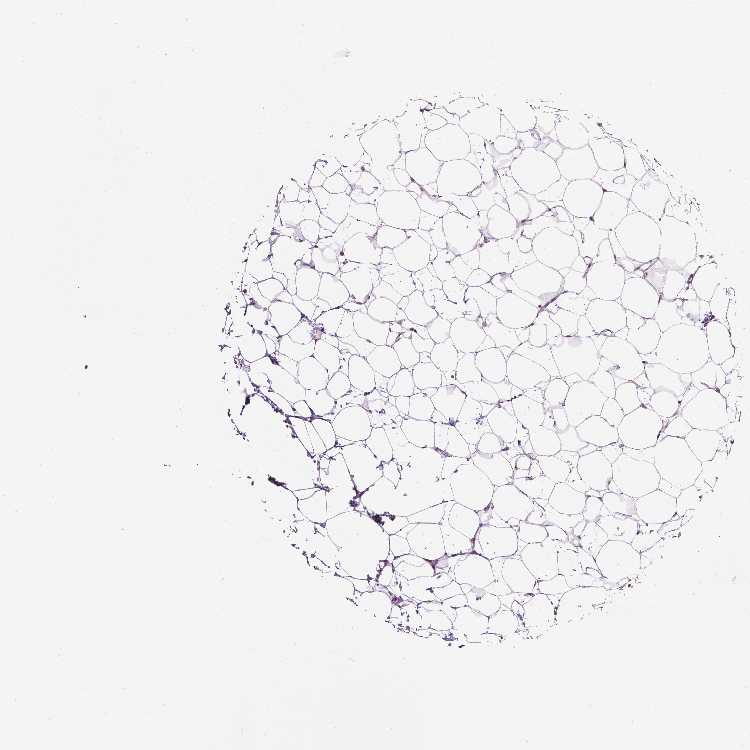

BREAST - Antibody stainingi

Antibody staining in the annotated cell types in the current human tissue is reported as not detected, low, medium, or high, based on conventional immunohistochemistry profiling in selected tissues. This score is based on the combination of the staining intensity and fraction of stained cells.

Each image is clickable and will lead to virtual microscopy that enables deeper exploration of all samples and also displays staining intensity scores, fraction scores and subcellular localization as well as patient and tissue information for each sample.

Antibody CAB019384

Adipocytes Medium

Glandular cells Low

Myoepithelial cells Low